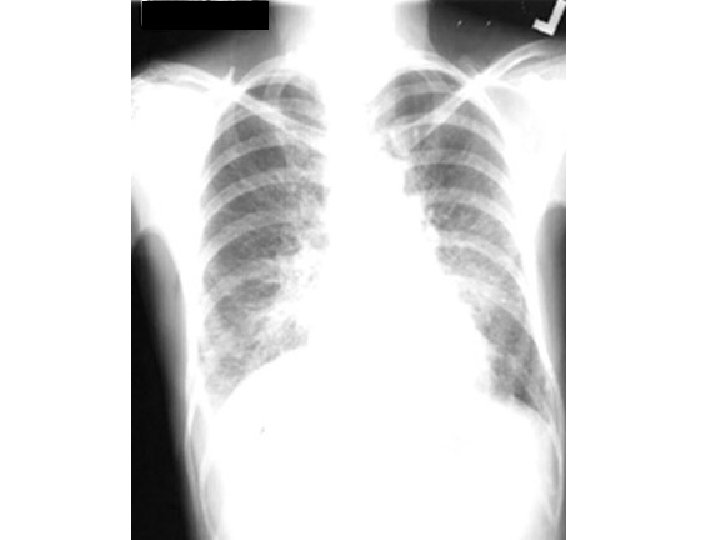

Pulmonary edema

Bilateral Diffuse Alveolar